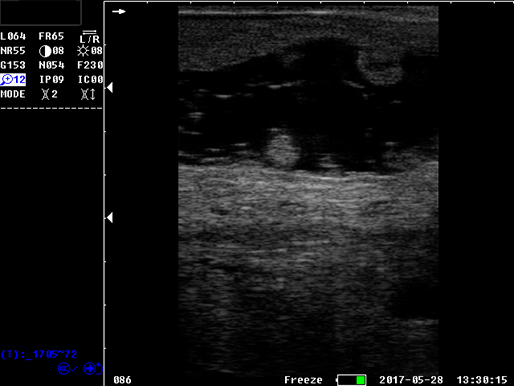

B模式 子宫 牛

B模式 牛 直肠

牛 直肠

牛未受孕

牛受孕泡

牛受孕35天